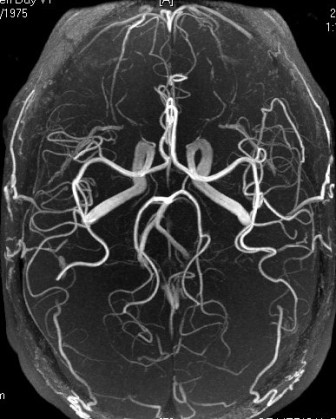

Однією з переваг магнітно-резонансної томографії, є можливість провести ангіографію (візуалізацію судин) без застосування контрастних препаратів. Зображення судин отримують завдяки відмінності сигналу від рухомої крові, в порівнянні з сигналом від нерухомих навколишніх тканин.

МР-ангіографія судин головного мозку